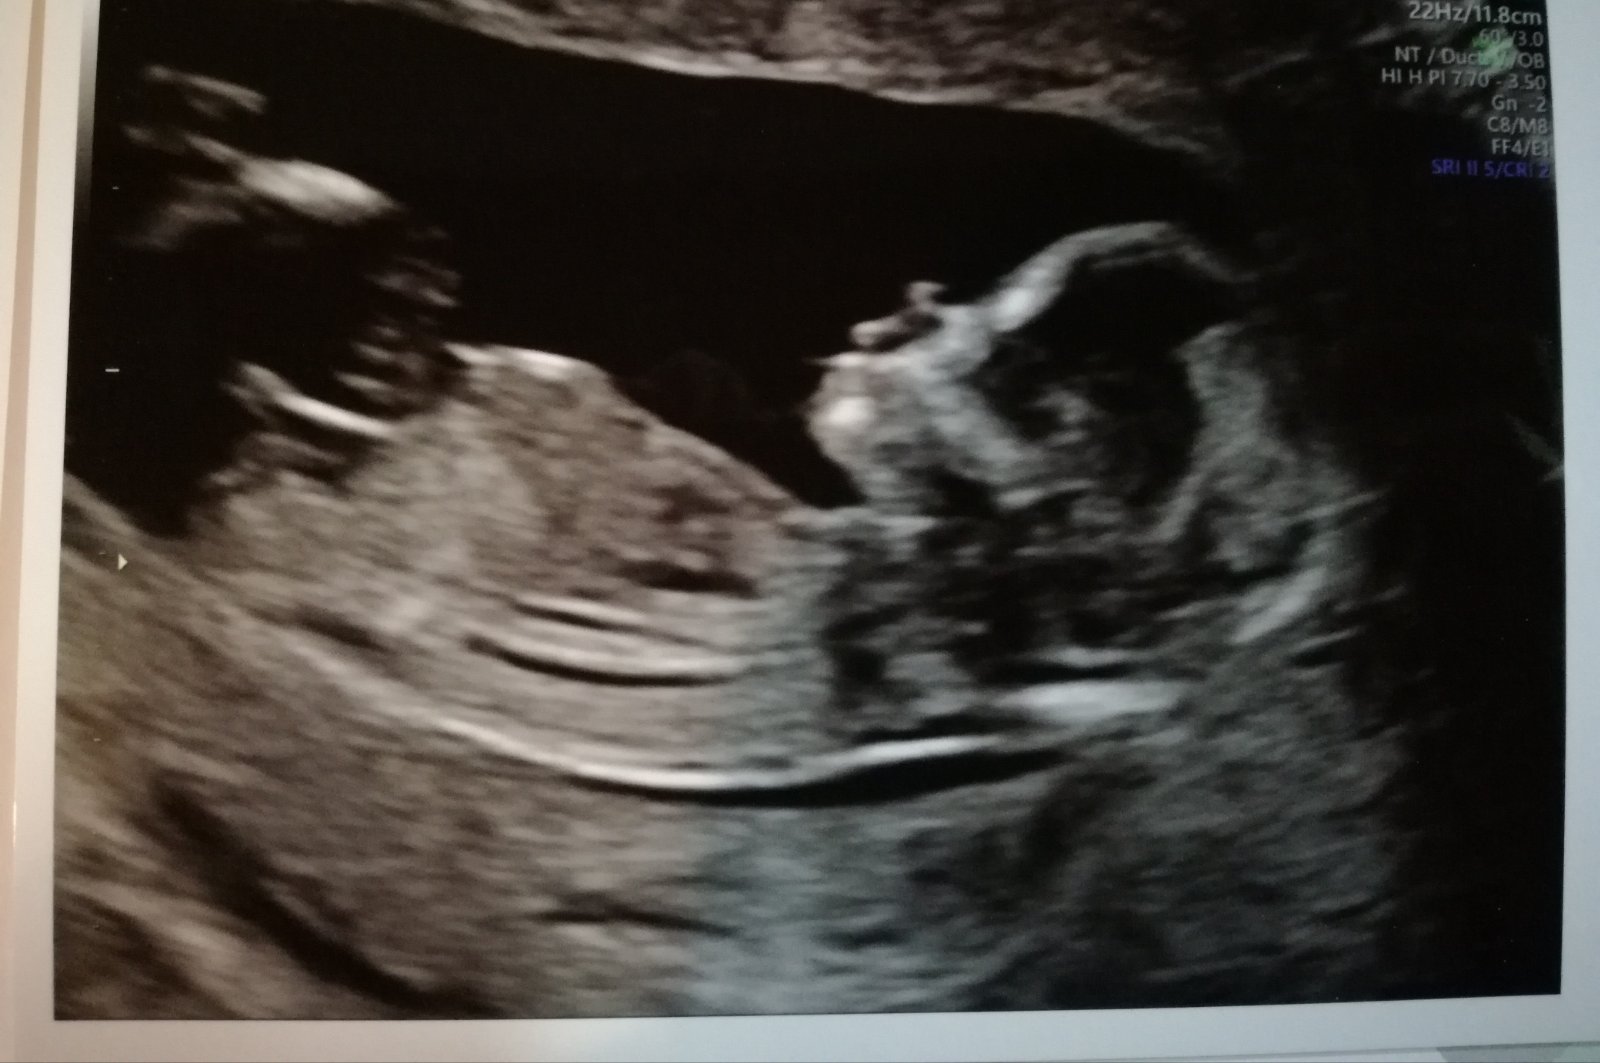

Pohlaví. Chlapeček nebo holčička?

Naše malá měla ten hrbolek krásně sklopenej, řekli nám 80 % slečna a vyšla.. tohle mi přijde na klučinu.. doktor se k tomu nevyjádřil?

Řekl na začátku chlapeček a když se pak miminko pohnulo, tak řekl holčička. A nakonec že neví 🙂. Taky si ale myslím, že to bude chlapeček.

Neřekli ti pravděpodobnost ? Nám to třeba řekli a trefili se. I když to bylo “jen” 60%